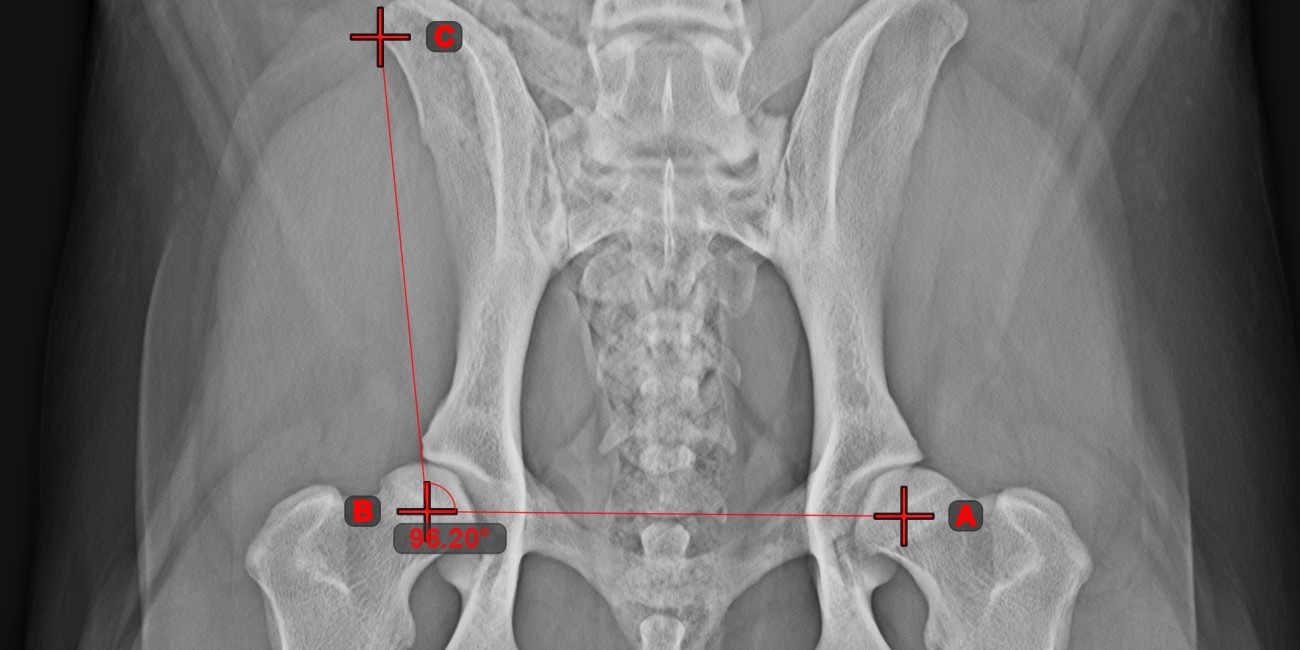

Calculate the angle between two independent or intersecting lines by using the Angle of Lines tool.

Select the tool from the left toolbar and assign it to one of the available mouse buttons. Start by selecting the first line from the ones already drawn on the scene, or place the start and end points to create the line. Follow the same steps for the second line of the measurement. The angle between the two lines will be automatically calculated.

Modify the start and end points of both lines by using the Select/Move Item tool. The angle between the two lines will be automatically recalculated.

Information

If two lines do not intersect directly, the angle of their extended projections on the scene will be calculated.

../_images/image7.jpg ../_images/image312.jpg